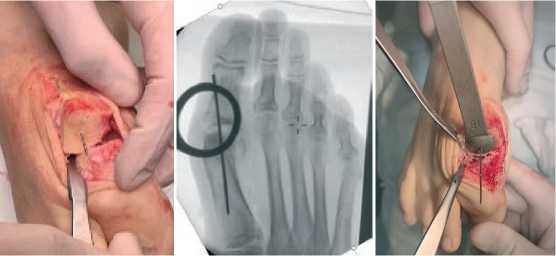

Положение пациента — на спине. Производится трёхкратная обработка операционного поля растворами антисептиков. Медиальным доступом выполняется артротомия первого плюснефалангового сустава (рис. 2).

Рис. 2 . Внешний вид сустава

Fig. 2 . External appearance of the joint

Осцилляторной пилой производится резекция костнохрящевых экзостозов, осуществляется мягкотканый релиз первого плюснефалангового сустава и сесамовидного гамака. С помощью резекционного блока оригинальной модели выполняется удаление пораженного участка суставной поверхности головки первой плюсневой кости до кровоснабжаемой губчатой костной ткани (рис. 3).

Рис. 3. Резекция суставной поверхности головки первой плюсневой кости с помощью резекционного блока Fig. 3. Resection of the articular surface of the head of the first metatarsal bone using a filing block

Следующим этапом производится пластика плюсне-сеса-мовидного сустава коллагеновой мембраной. Выполняется резекция измененной суставной поверхности головки первой плюсневой кости со стороны плюсне-сесамовидного сустава, выполняется её остеоперфорация по Бэку спицей диаметром 1 мм до появления «кровяной росы». При необходимости выполняется резекция по плоскости гипертрофированных сесамовидных костей. Осуществляется примерка и адаптация коллагеновой мембраны под площадь поверхности плюсне-сесамовидного сустава. Далее возможны два варианта фиксации коллагеновой мембраны. В первом случае применяют фибриновый клей, с помощью которого происходит фиксация коллагеновой мембраны к сформированно- му ложу. Фибриновый клей наносится на субхондральную кость, полностью заполняя область имплантации мембраны. Поверх укладывается коллагеновая мембрана, происходит выжидание экспозиции для застывания клея.

Второй вариант фиксации предполагает фиксацию рассасывающимся шовным материалом. С помощью спиц диаметром 1 мм. выполняется 4 отверстия в плюсневой кости в дорсально-плантарном направлении. Через отверстия проводится рассасывающаяся полифиламентная нить 4.0. Коллагеновая мембрана прошивается шовным материалом и фиксируется на узлах к плюсневой кости. С помощью импактора производится press-fit установка гемиэндопротеза (рис. 6).

Рис. 6 A. Прошивание коллагеновой мембраны и её ориентирование на первой плюсневой кости. В. Внешний вид стопы после установки гемиэндопротеза и пластики плюсне-сесамовидного сустава коллагеновой мембраной

Fig. 6 . A. Suturing the collagen membrane and orienting it on the first metatarsal bone. B. Appearance of the foot after installation of the hemiendoprosthesis and plastic surgery of the metatarso-sesamiod joint with a collagen membrane

б

После установки гемиэндопротеза выполняют повторную оценку амплитуды движения в суставе, оценивают фиксацию коллагеновой мембраны (Рис 7).

Рис. 7. Интраоперационная оценка амплитуды движений

1 ПФС после гемиэндопротезирования 1 ПФС и пластики плюсне-сесамовидного сустава коллагеновой мембраной Fig. 7 . Intraoperative assessment of the range of motion of the 1 MTP joint after hemiendoprosthetics of the 1 MTP joint and plastic surgery of the metatarso-sesamoid joint with a collagen membrane